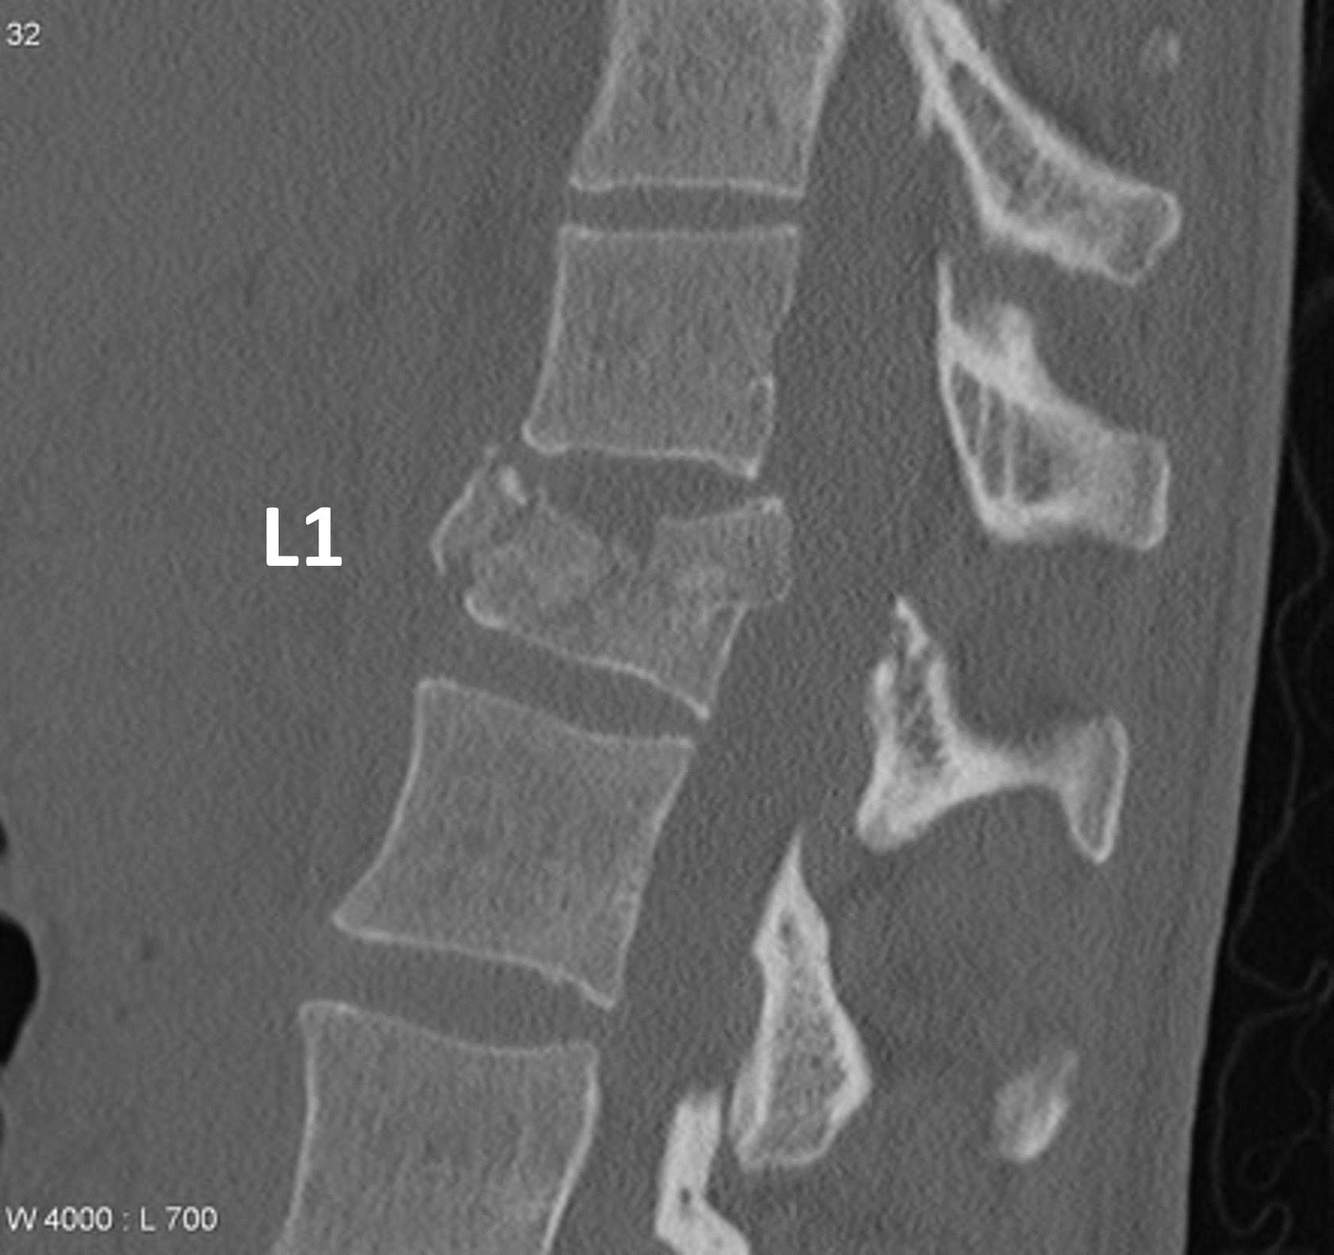

What is the most accurate description of this CT of the thoraco-lumbar spine?

a) There is significant anterior displacement of L1 compared to L2

b) The mechanism of injury is unlikely to be axial loading

c) This is a burst fracture

d) There is no risk of spinal cord injury

e) Normal CT

A